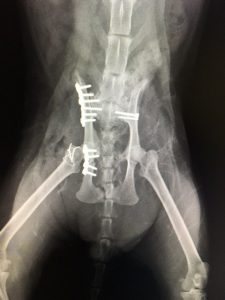

猫の骨盤骨折